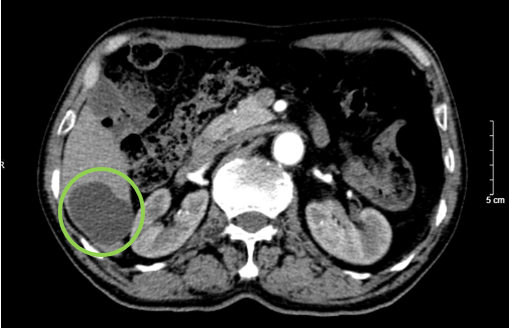

Hình 3. Hình ảnh nang gan kích thước 49x35mm (vòng tròn xanh lục) tại nhu mô gan phải hạ phân thùy VI trên phim chụp cắt lớp vi tính ổ bụng có thuốc cản quang thì động mạch.

Hình 4. Tuyến tiền liệt tăng kích thước (hình tròn màu xanh), có phần lồi vào bàng quang (mũi tên xanh) trên phim chụp cắt lớp vi tính ổ bụng thì động mạch.